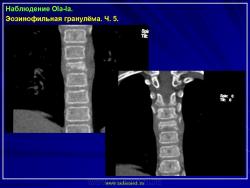

Продолжение.

1.gi_.slayd14.jpg2.gi_.slayd15.jpg3.gi_.slayd16.jpg1.gis_.slayd15.jpg2.gis_.slayd16.jpg3.gis_.slayd17.jpg4.gis_.slayd18.jpg5.gis_.slayd19.jpg6.gis_.slayd20.jpg7.gis_.slayd21.jpg8.gis_.slayd22.jpg9.gis_.slayd23.jpg